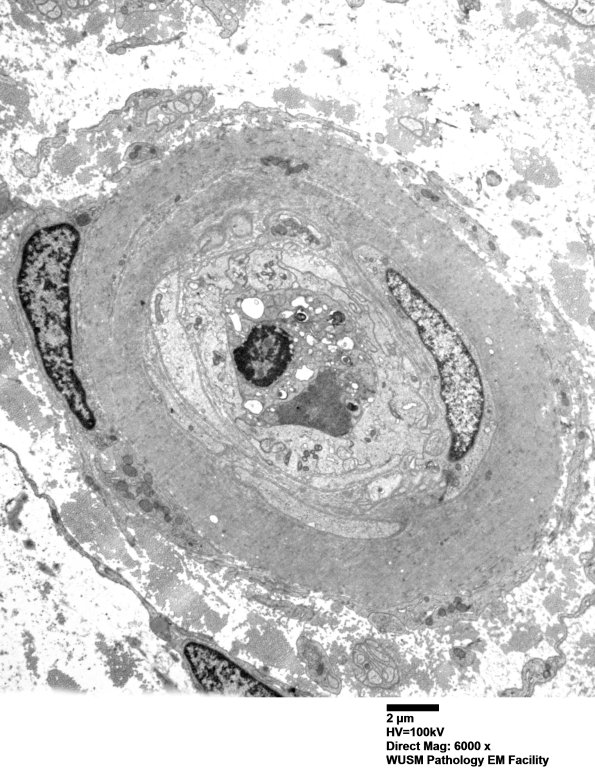

Washington University Experience | VASCULAR | Hypoxia-Ischemia, fetal-neonatal | White Matter | 5C4 (Case 5) EM062 - Copy

5C4 (Case 5) EM062 - Copy